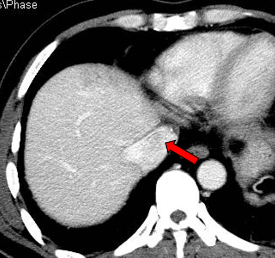

2011-01-06我院上腹部CT:

肝左叶巨块型肝癌(13.8cm×9.1cm),伴肝右后叶子灶,门静脉左支、肝左静脉及下腔静脉内癌栓。